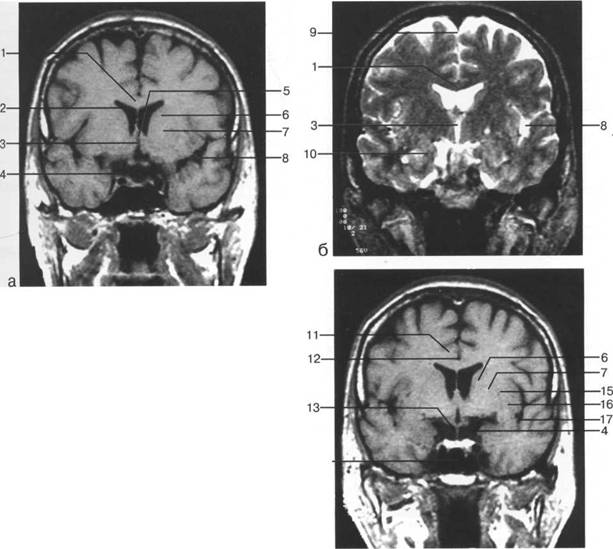

Задняя череп 13513u2010n 85;ая ямка представляет собой часть основания череп 13513u2010n 72;, ограниченную централь

Следует отметить, что в настоящее время оптимальным методом исследования структур задней череп 13513u2010n 85;ой ямки является МРТ, которая, в отличие от КТ, лишена артефактов от кост

Мозжечок заполняет практически весь объем задней череп 13513u2010n 85;ой ямки. Его поперечный раз

височная доля; 17 - полушарие мозжечка; 18 - |

Следует остановиться на анатомии подпаутинных пространств задней череп 13513u2010n 85;ой ямки IV 20 мм. Между основанием череп 13513u2010n 72; и нижней поверхностью мозга от большого затылочного отверстия вдоль ската и спинки турецкого седла простирается задняя базальная цистерна. В зави IV